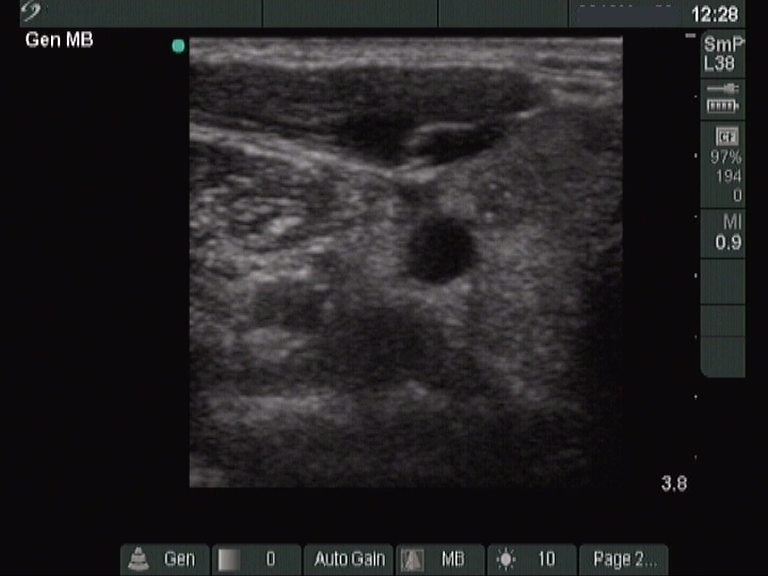

Longitudinal scan |

According to the EU-TIRADS, this lesion cannot be regarded as a purely cystic nodule due to the presence of wall-thickening (yellow arrows). The EU-TIRADS defines this lesion as an EU-TIRADS 3 nodule.